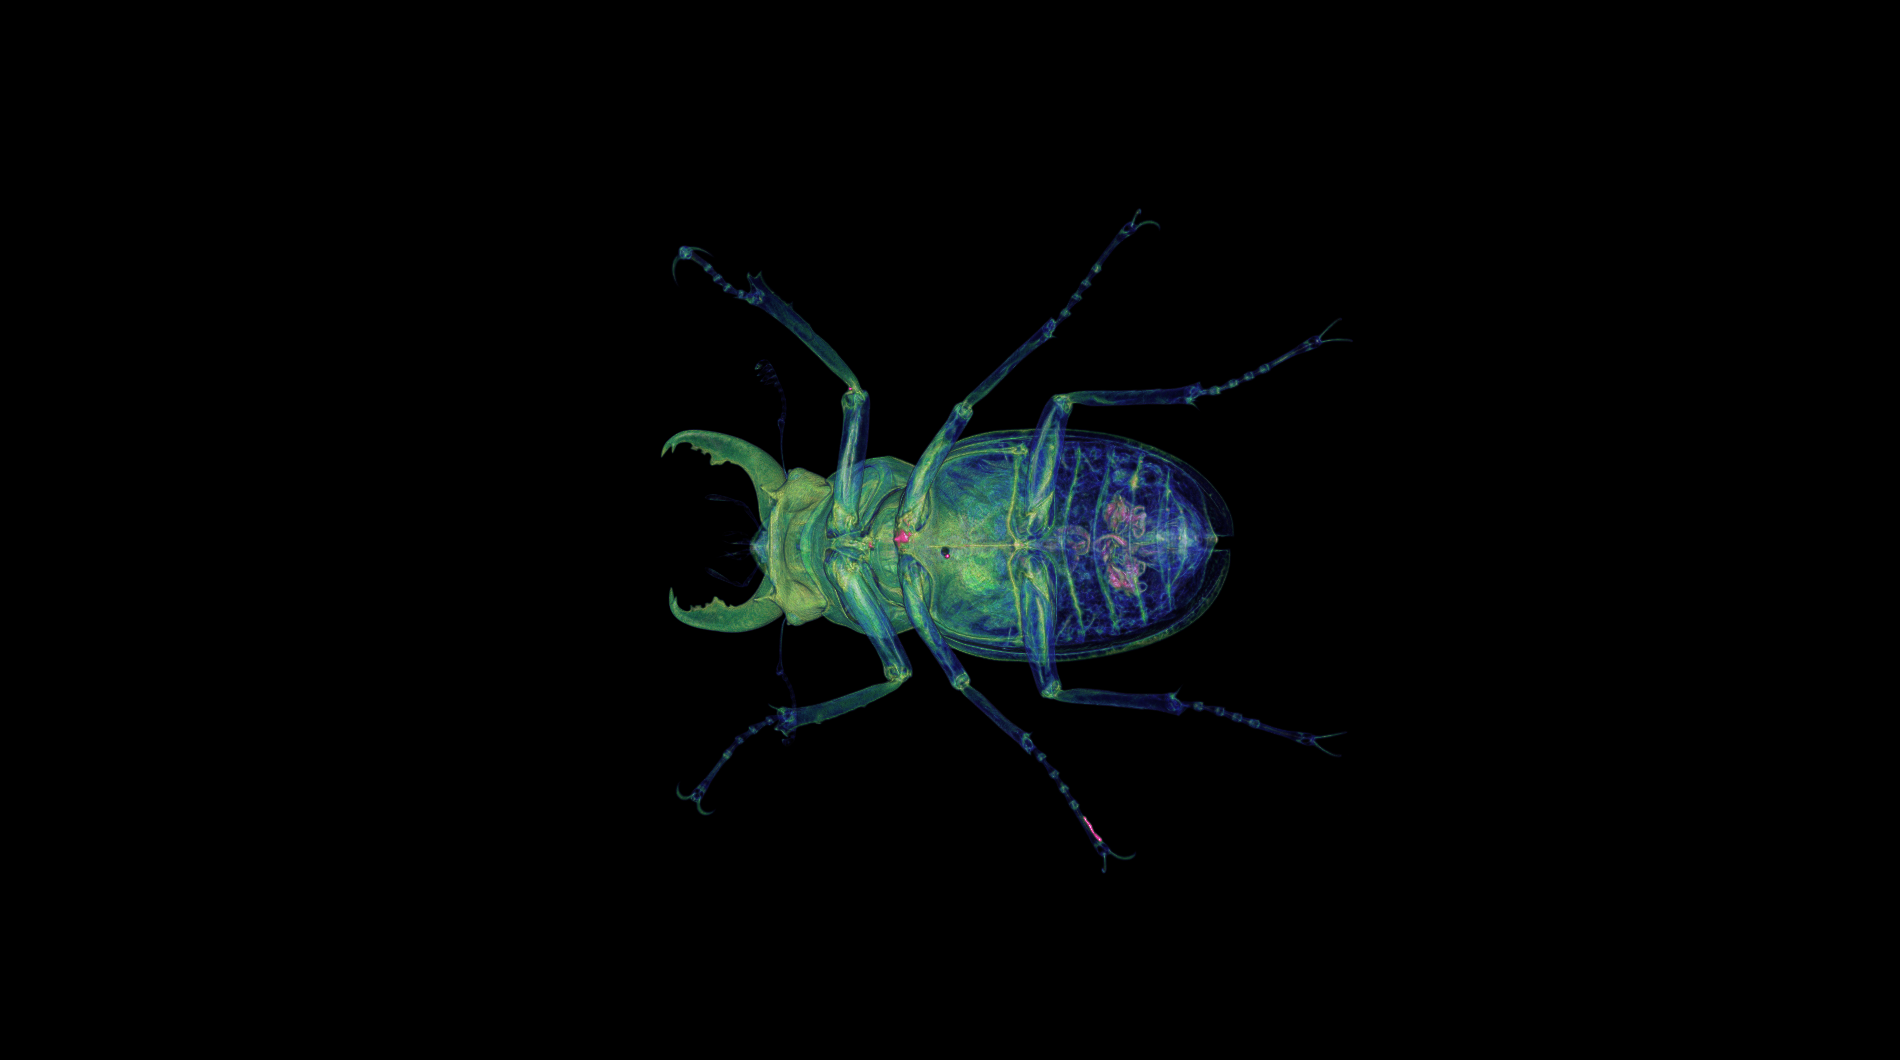

medical-03

The medical-03 viewset demonstrates the performance of several medical visualization volume rendering techniques. The first is "slice rendering", where many 2D slices are projected through the volume and composited on the screen. The second is "raycasting" where rays are projected through the volume accumulating the final pixel color. Two different transfer functions are used: 1D, where the density is used to look up each voxel color, and 2D, where density and gradient magnitude are used to look up each voxel color. A clipping plane is used in several tests. The Tuvok visualization library is used for rendering.

medical-03 composite score: 25.67

The composite score is a weighted geometric mean of the subtest scores. See the table below for subtest weights and FPS scores for this run.

Subtest results

Click on each thumbnail image below to display the subtest's screen grab.

The results table above includes the details about each test within a viewset. Viewsets are often comprised of many tests which produce a frame rate. Frame rate is computed as the average Frames Per Second (FPS), or the total number of frames rendered divided by the time in seconds to render those frames. These FPS values are then used to compute the composite score using the weights for each test.